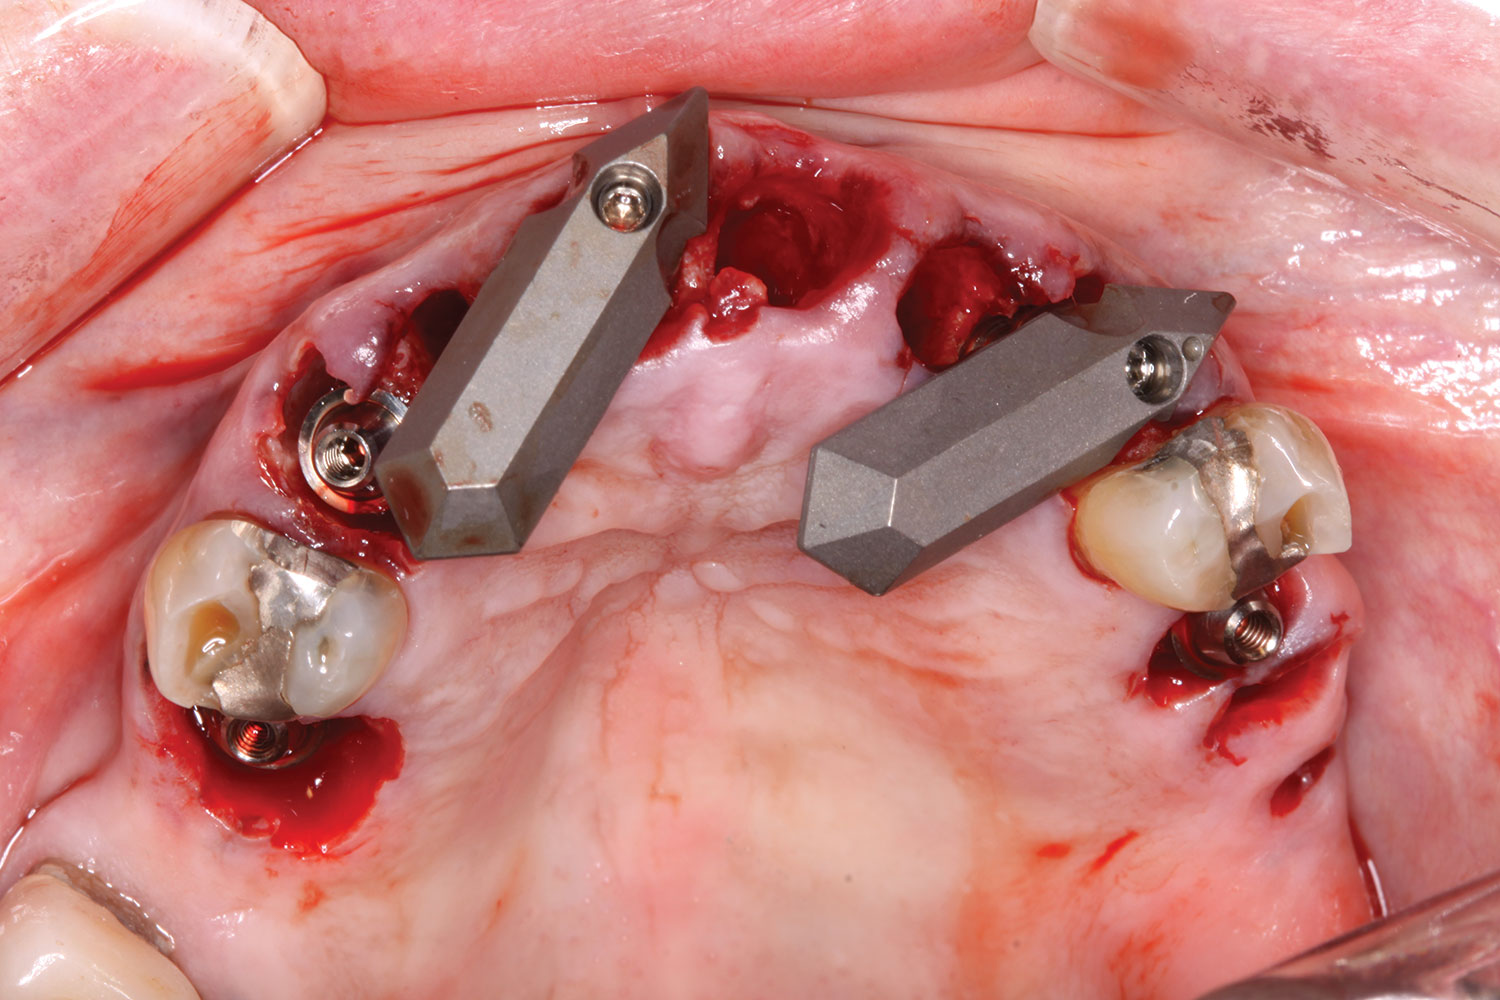

At the following visit, the patient was anesthetized with xylocaine with 1:100,000 epinephrine. Teeth Nos. 4, 6, and 11 were extracted, and immediate implants with multi-unit abutments were placed prosthetically correctly with favorable insertion torques in sites Nos. 6 and 11 (Figure 3). Scan gauges were attached to the multi-unit abutments, and a scan was taken to capture the location of the implants with a reference to the remaining teeth with capture of the soft tissues.

Scan gauges were then attached to the multi-unit abutments on the remaining implants so that all the implants were now in place with scan gauges (Figure 4). A scan was taken to capture all of the implants and surrounding soft tissue. The scanning protocol calls for scanning left to right, and then a separate scan right to left. These files were then sent electronically to the proprietary web portal.

Fig 3. Initial extractions and scan gauges in place on multi-unit abutments secured to underlying implants.

Figure 3

Fig 4. Extractions completed; all implants, multi-unit abutments, and scan gauges in place.

Figure 4